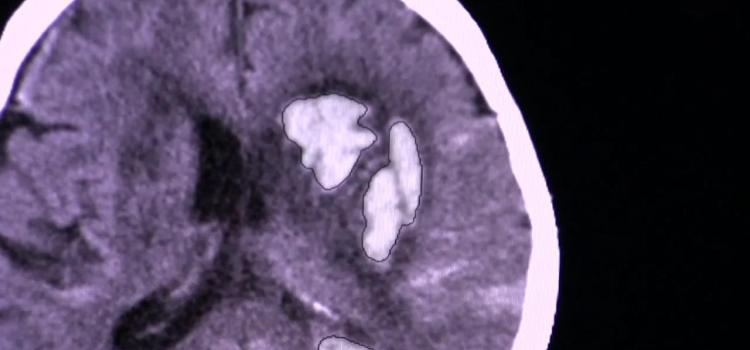

Radiomics is the study of information hidden in imaging exams that machine algorithms are trained to identify to help doctors more accurately diagnose patients, stage cancers, determine optimum therapies, predict patient outcomes or their risk level choose the radiation therapy dose level of risk. The field of medical study extracts large amounts of quantitative features from medical images using data characterization algorithms. These features, called radiomic features, may be able to uncover disease characteristics that fail to be appreciated by the naked eye. It is expected this field will be dominated by artificial intelligence software in the coming years.

July 30, 2014 — Information hidden in imaging tests could help doctors more accurately choose the radiation therapy dose ...